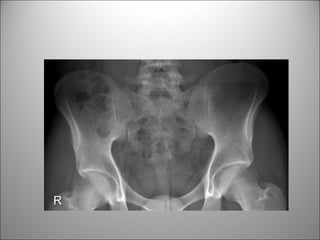

TEJIDO BLANDO

• Visión limitada de estructuras-órganos

• Puede verse +/-

– Hígado

– Bazo

– Riñones

– Psoas

– Vejiga

– Bases pulmonares

HUESOS